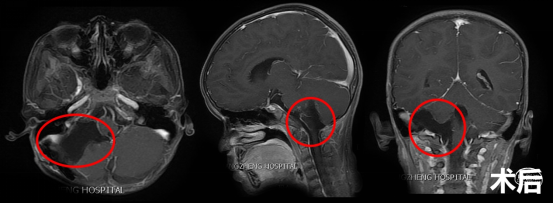

儿童四脑室巨大室管膜瘤的显微外科手术病例_小儿脑肿瘤_治疗方式

图片尺寸2000x668